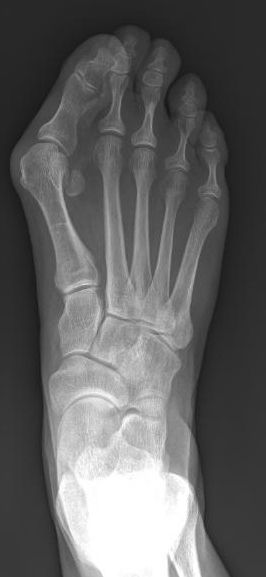

Radiografías

Las radiografías ofrecen imágenes de estructuras densas, como los huesos. Una radiografía le permitirá al médico comprobar la alineación de los dedos y buscar daños en la articulación MTF.

La alineación de los huesos del pie cambia cuando se pone de pie o se sienta. El médico tomará una radiografía mientras esté de pie para ver con más claridad el defecto de alineación de los huesos del pie. Usará las radiografías para determinar cuán grave es el juanete y cómo corregirlo mejor.

Las radiografías del pie le muestran al médico qué tan desalineados están los huesos.

Reproducido de Wagner E, Ortiz C: Proximal oblique sliding closing-wedge osteotomy for wide-angle hallux valgus. Orthopaedic Knowledge Online Journal: Vol 12, No 4, 4/1/2014; Accessed December 2015.